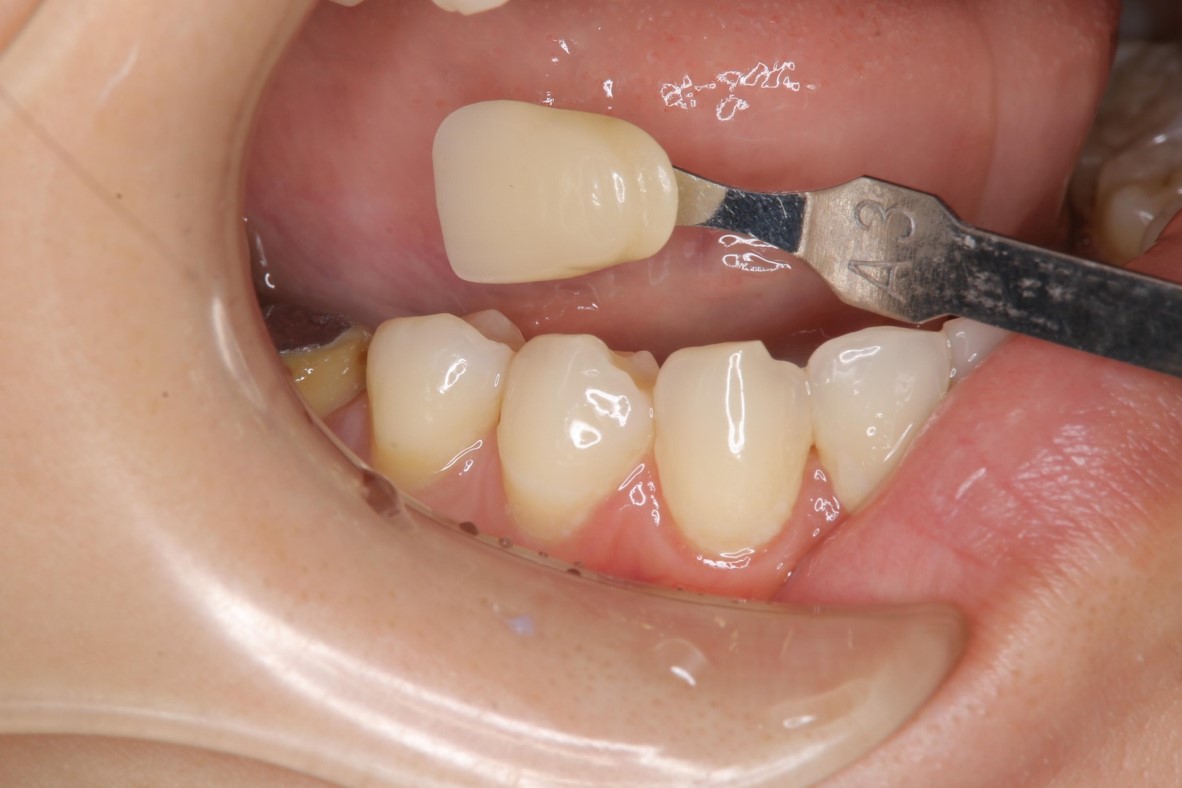

膺復前評估牙齦、牙齒狀態

照相比色

全鋯冠

治療後,牙周咬合良好

治療後,密合度良好